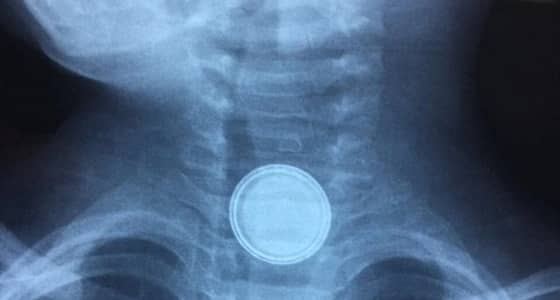

مستشفى عرعر

بالصور.. طفل يبتلع ” بطارية حديدية ” في عرعر